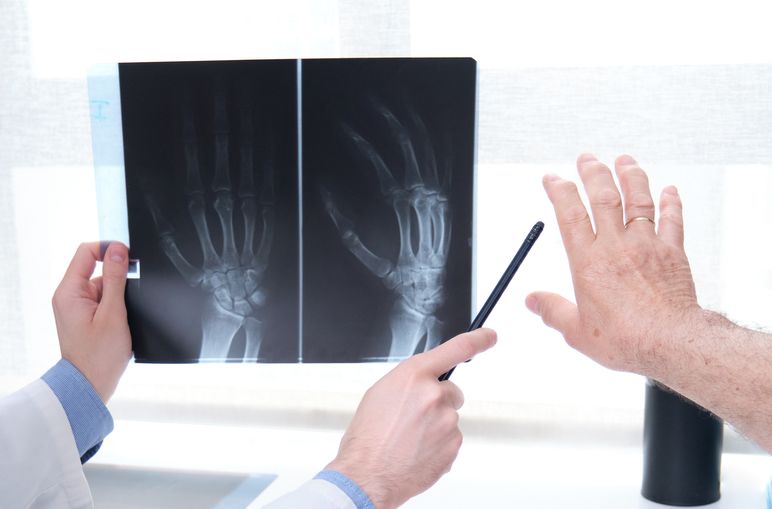

Как делают рентген кисти

Вся процедура выполняется в диагностическом кабинете. Предварительно пациент выбирает подходящий день и записывается. Рентген кисти полностью лишен боли и неприятных ощущений. Нет необходимости вводить контраст. После того как рентген кисти руки завершится, можно сразу направляться по своим делам.

Этапы рентгена кости кисти руки:

- Специалист подготавливает аппарат. Провожает человека к оборудованию.

- Пациент садится на стул. Руку сгибает в локте, кладет на кассету. Для неподвижности конечности дополнительно используется фиксирующее устройство. Соседние участки тела защищаются свинцовым фартуком.

- Рентгенолог размещается в другой комнате. Сначала он делает рентген кисти в прямой проекции. Это позволяет увидеть крупные кости. Далее выполняется рентгенография в боковой проекции. Что позволяет изучить более мелкие костные структуры на периферии. При необходимости дополнительно получают изображения в косой проекции.

- Исследование завершается. Больной одевается. Он остается в коридоре и ждет результаты.

- Врач оформляет протокол. Печатает снимки. Отдает все сведения пациенту.